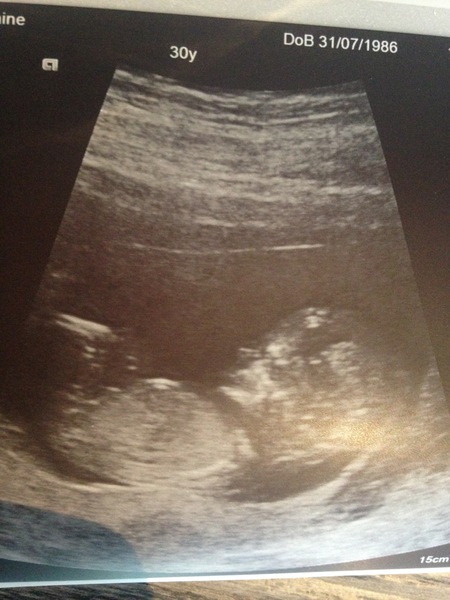

My scan also went well, big relief. Very lazy baba. EDD 6th March. I am now driving myself insane because there are 3 bright white lines in groin but not on a transverse view so is it a girl?! DH is not happy with me for investigating the sex already Confused

Glad your scans went well too ladies :) I can't tell anything from my scan pic but am open to guesses!

Yesterday's scan couldn't have gone better, the sonographer was lovely (unlike the one I had last time, so I was pleasantly surprised). She actually seemed to enjoy her job, and explained everything we were looking at. Baby was very well behaved and she had no trouble getting measurements. She also got what looks like a good nub photo (not that I'm an expert) and I've been driving OH mad by guessing the sex (even though we're not going to find out)!